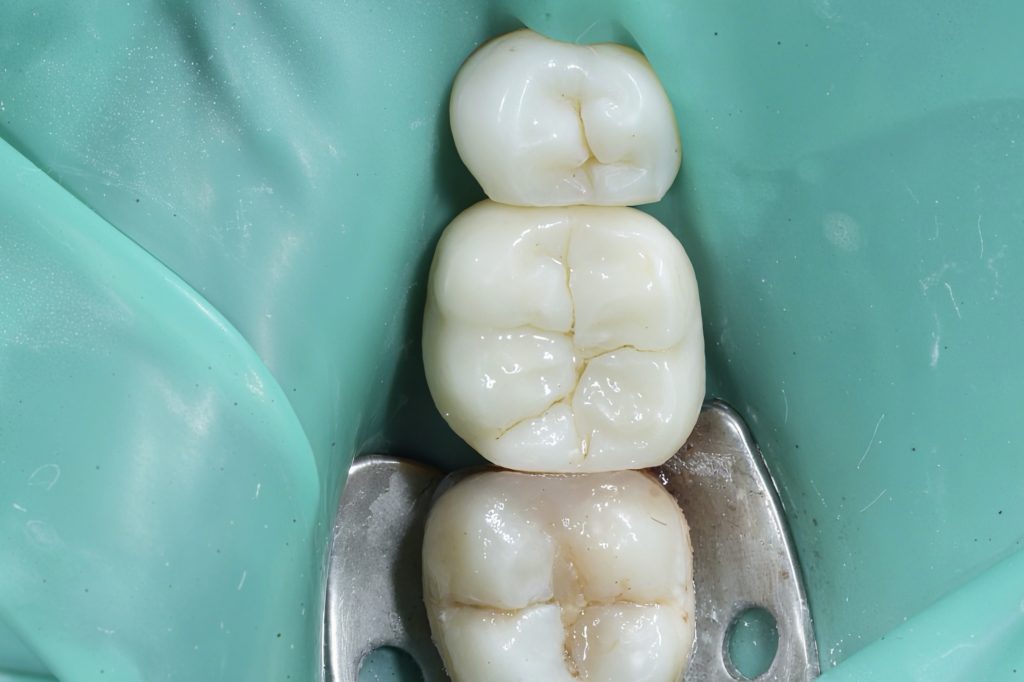

5️⃣ Occlusal Anatomy & Finishing

The enamel replacement was sculpted using Tokuyama Estelite Sigma Quick A2/A3 shades, carefully replicating fissure architecture and line angles under microscope-assisted magnification.

Final contouring and gloss were obtained with Dentsply Enhance Finishing System, PoGo, and Lucida Polishing Paste.

3️⃣ Composite build-up and occlusal layering